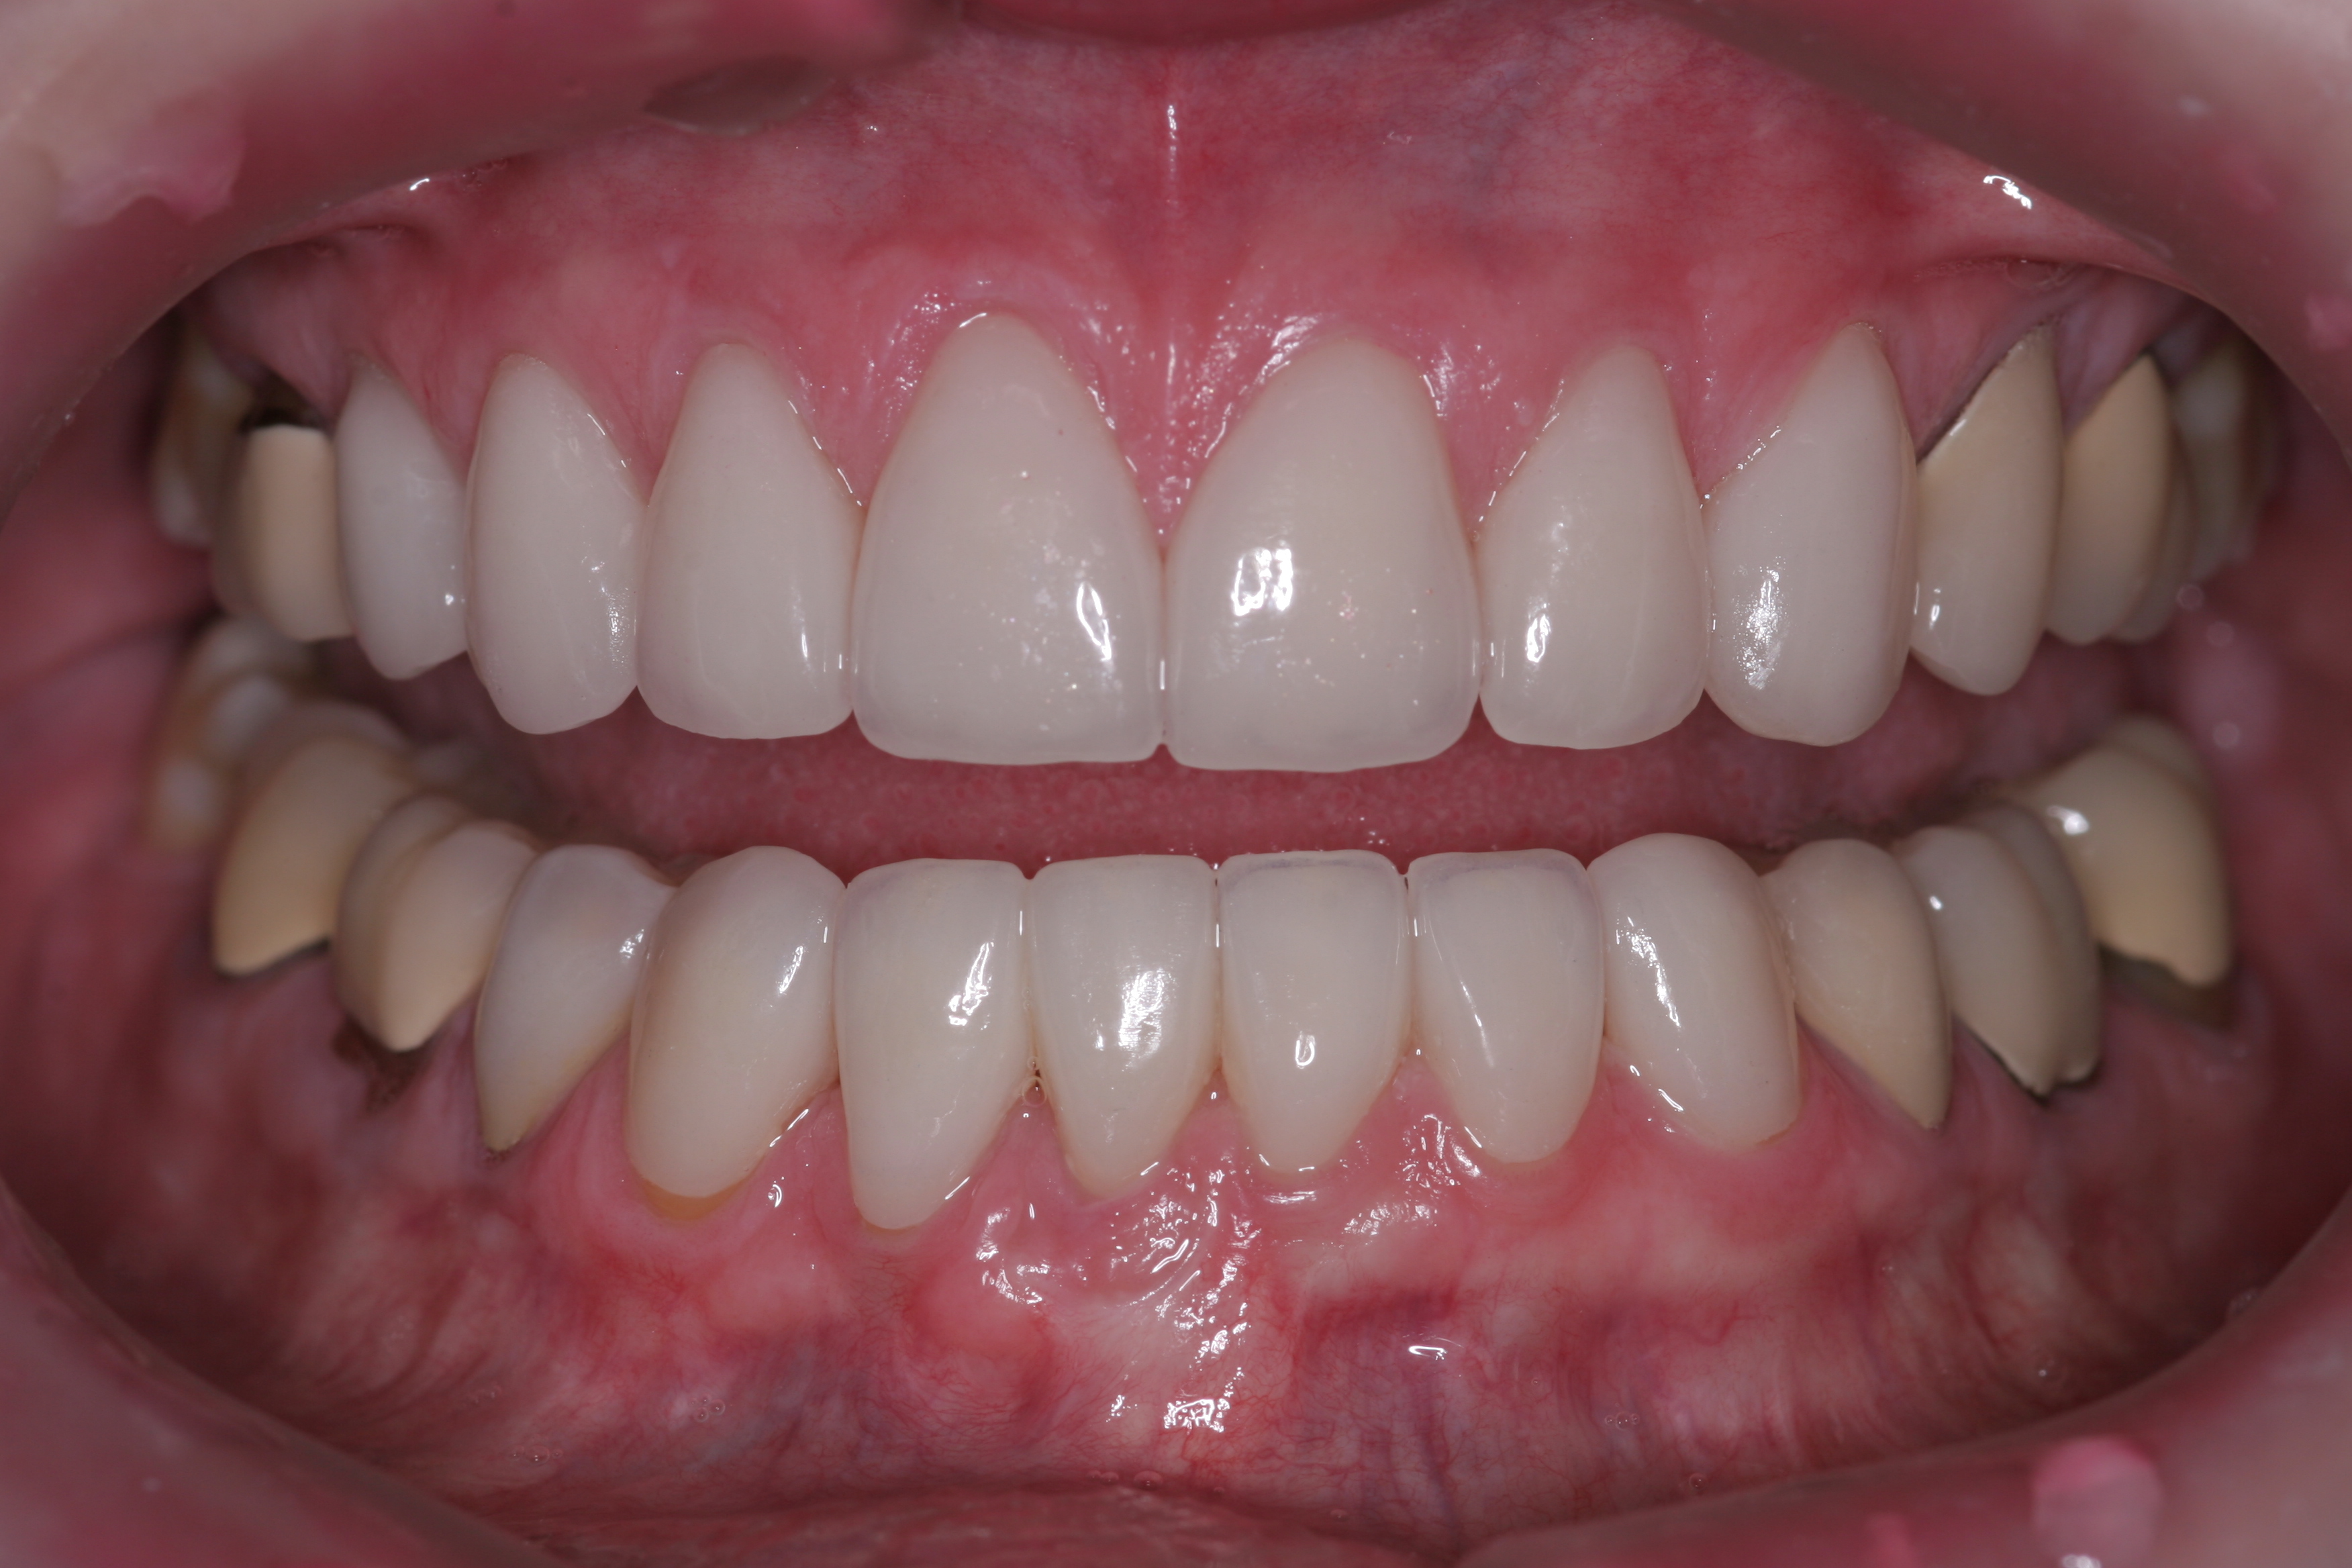

(22.) The final restorations, which reflect the changes modeled through the provisional phase.

Figure 22

(23.) The final restorations, which reflect the changes modeled through the provisional phase.

Figure 23

Once approved, impressions of the provisionals were taken so the laboratory could precisely copy the 3D position of the anterior teeth as successfully proven in the provisionals. The postoperative result and final functional photographs are shown in Figure 22 through Figure 29. Posterior treatment can now be completed in segments as necessary. Posterior morphology will be developed in harmony with the now corrected anterior contour and functional parameters. The fulfillment of the previously mentioned requirements of occlusal stability were evaluated and refined in the final restorations. The patient was placed in a posttreatment dual-arch B splint appliance to help manage any further parafunctional forces should they occur.